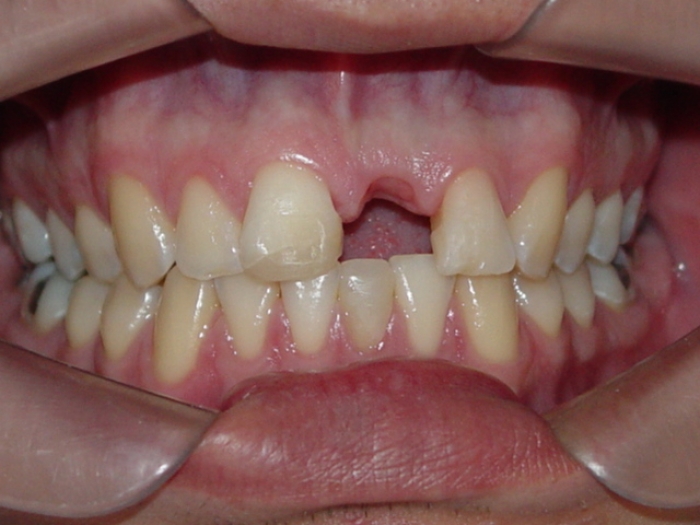

Imagem final do caso terminado em Agosto de 2013

Sorriso final